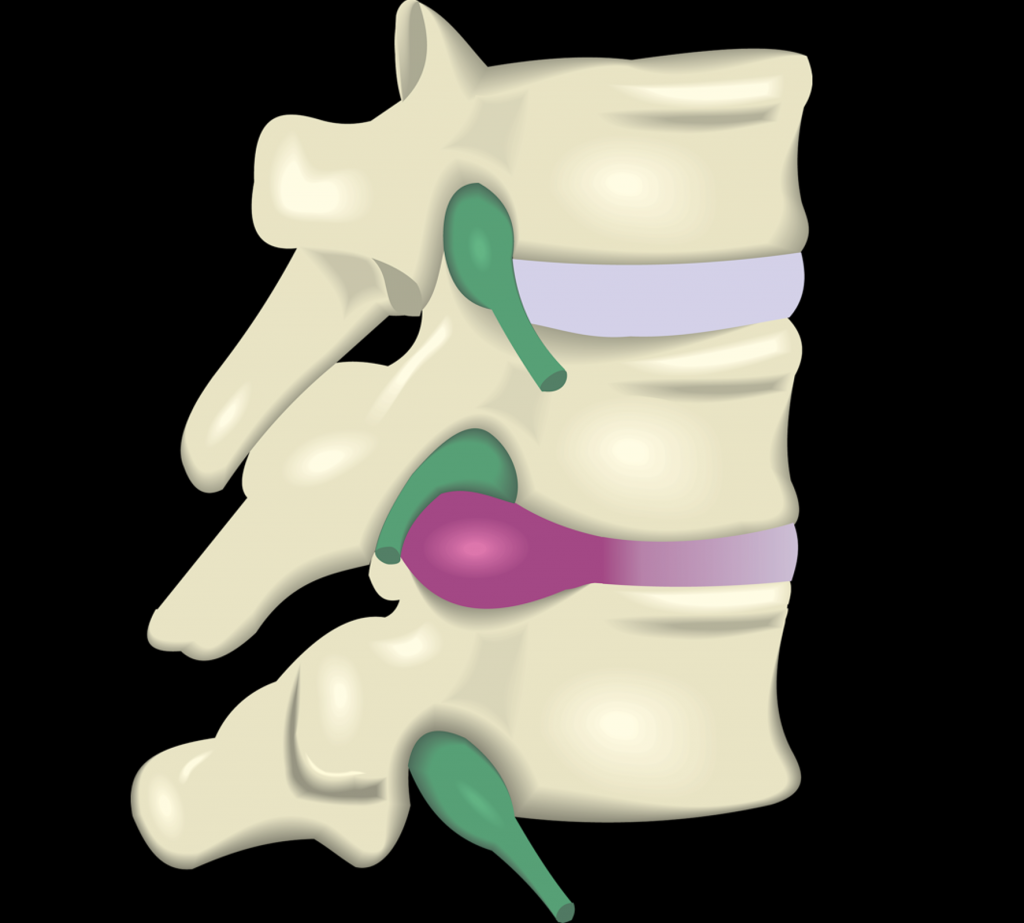

Bulging and Herniated Discs – Explained | Physical Health Care

What is the difference between a bulging disc and a herniated disc?

Herniated Bulging Disc